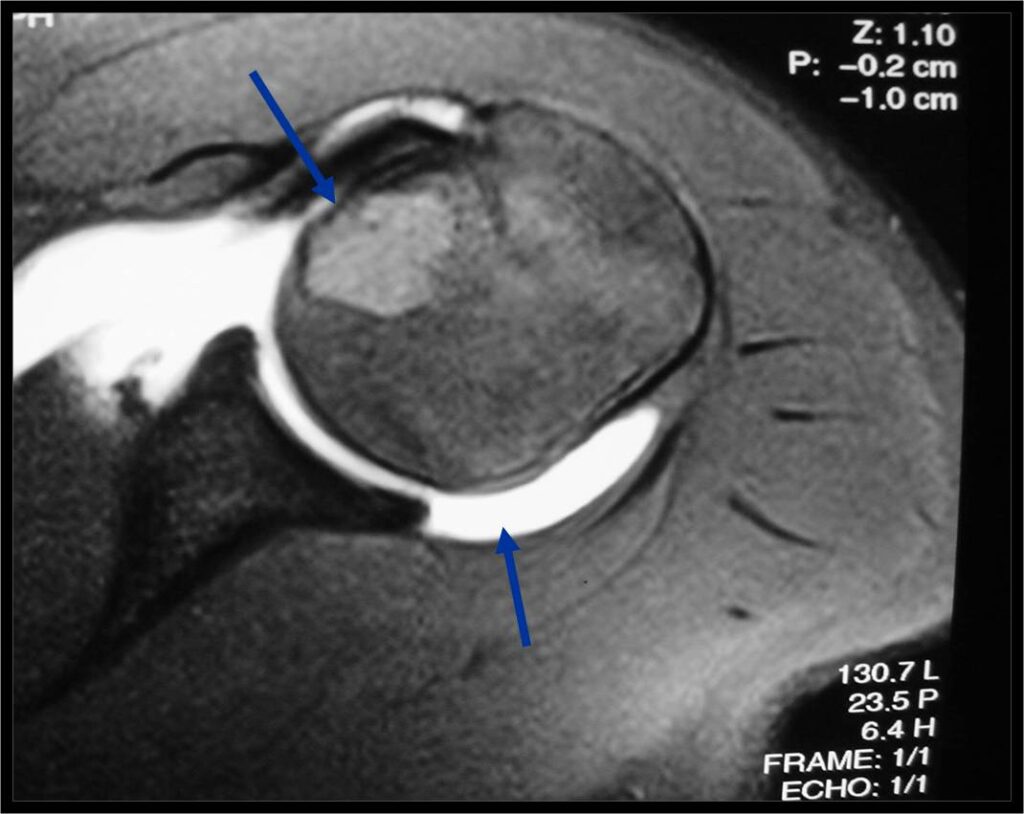

- (MRI appearance)

- Geographic, well circumscribed lesion in the epiphysis

- Intermediate Signal on T1

- High signal on T2 mixed with low signal areas (low signal areas proposed to be secondary to lysosomal content of highly cellular areas)

- Fluid/Fluid levels demonstrated in tumors that have undergone ABC change (aneurysmal bone cyst change)

- Extensive Surrounding edema is common

- Joint effusion in 30-50% of cases